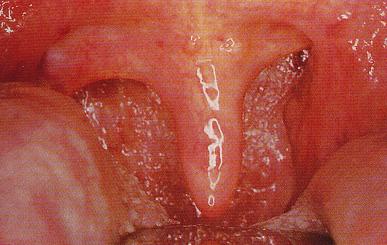

图为:扁桃体脓肿

医生介绍,发生在扁桃体周间隙的化脓性炎症,称为扁桃体周脓肿。初起为蜂窝织炎(称为扁桃体周炎),继之形成脓肿。多见于青、中年患者。